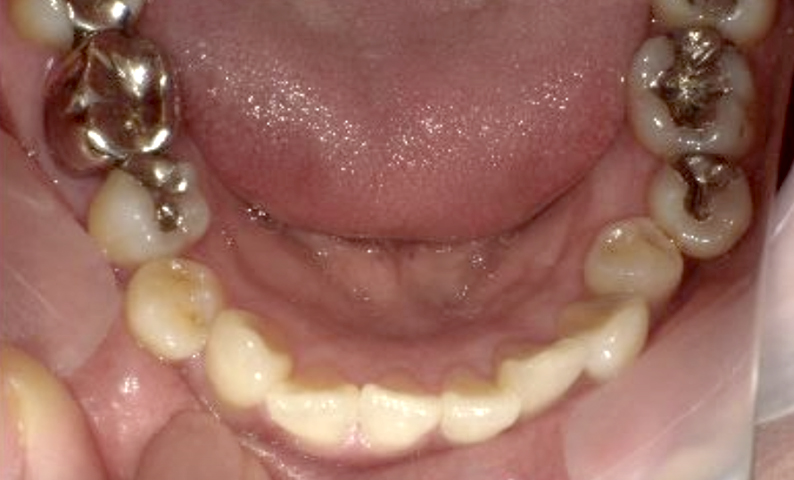

症例_003 下顎だけの部分矯正

治療期間:10ヶ月金額:24万円+税女性前歯のガタガタ下の前歯だけ上顎は補綴治療中

| Before | After |